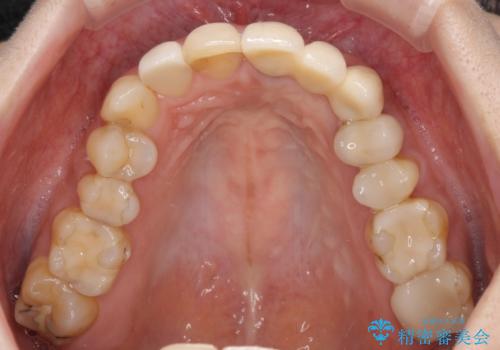

歯肉移植を用いた前歯のオールセラミックブリッジ

- 前歯が折れてしまい、ブリッジによる補綴治療を希望して来院された患者様です。

折れている前歯は抜歯をし、痩せてしまう歯肉は移植術により増大させることで審美面を回復した後、オールセラミックブリッジにて補綴することとしました。

インプラントかブリッジか悩むところでしたが、既に治療されている前歯のクラウン周りの変色が気になっていたため、ブリッジにより色調を合わせたオールセラミックを装着することを選択しました。

歯肉ラインや歯の形態、色調を整えることができ、患者様には大変満足していただきました。